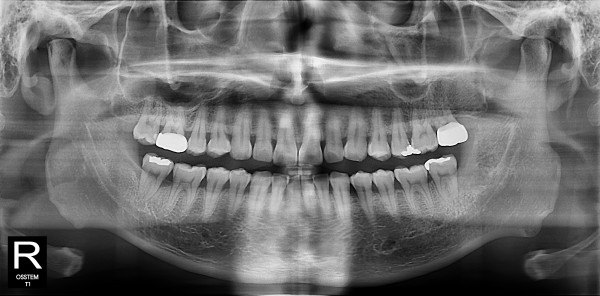

사랑니발치 20대/남성

5e20e086184bc11a2d853605b7813944_1764319731_1428.jpg